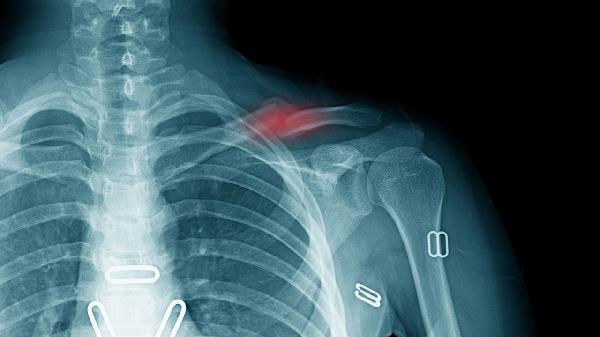

脚背撕脱骨折可通过制动固定、冷敷处理、药物治疗、康复训练、手术治疗等方式治疗。脚背撕脱骨折通常由剧烈运动损伤、直接外力撞击、肌腱牵拉、骨质疏松、骨骼发育异常等原因引起。

使用支具或石膏固定患处4-6周,避免关节活动加重骨折移位。固定期间需定期复查X线片观察愈合情况,若出现固定松动或皮肤压迫需及时调整。夜间睡眠时可抬高患肢15-20厘米促进静脉回流。

对于骨折块移位超过3毫米或合并关节面损伤者,需行切开复位内固定术。术后2周开始渐进性负重,使用锁定钢板者可早期活动。高龄患者需评估骨密度,必要时联合抗骨质疏松治疗。